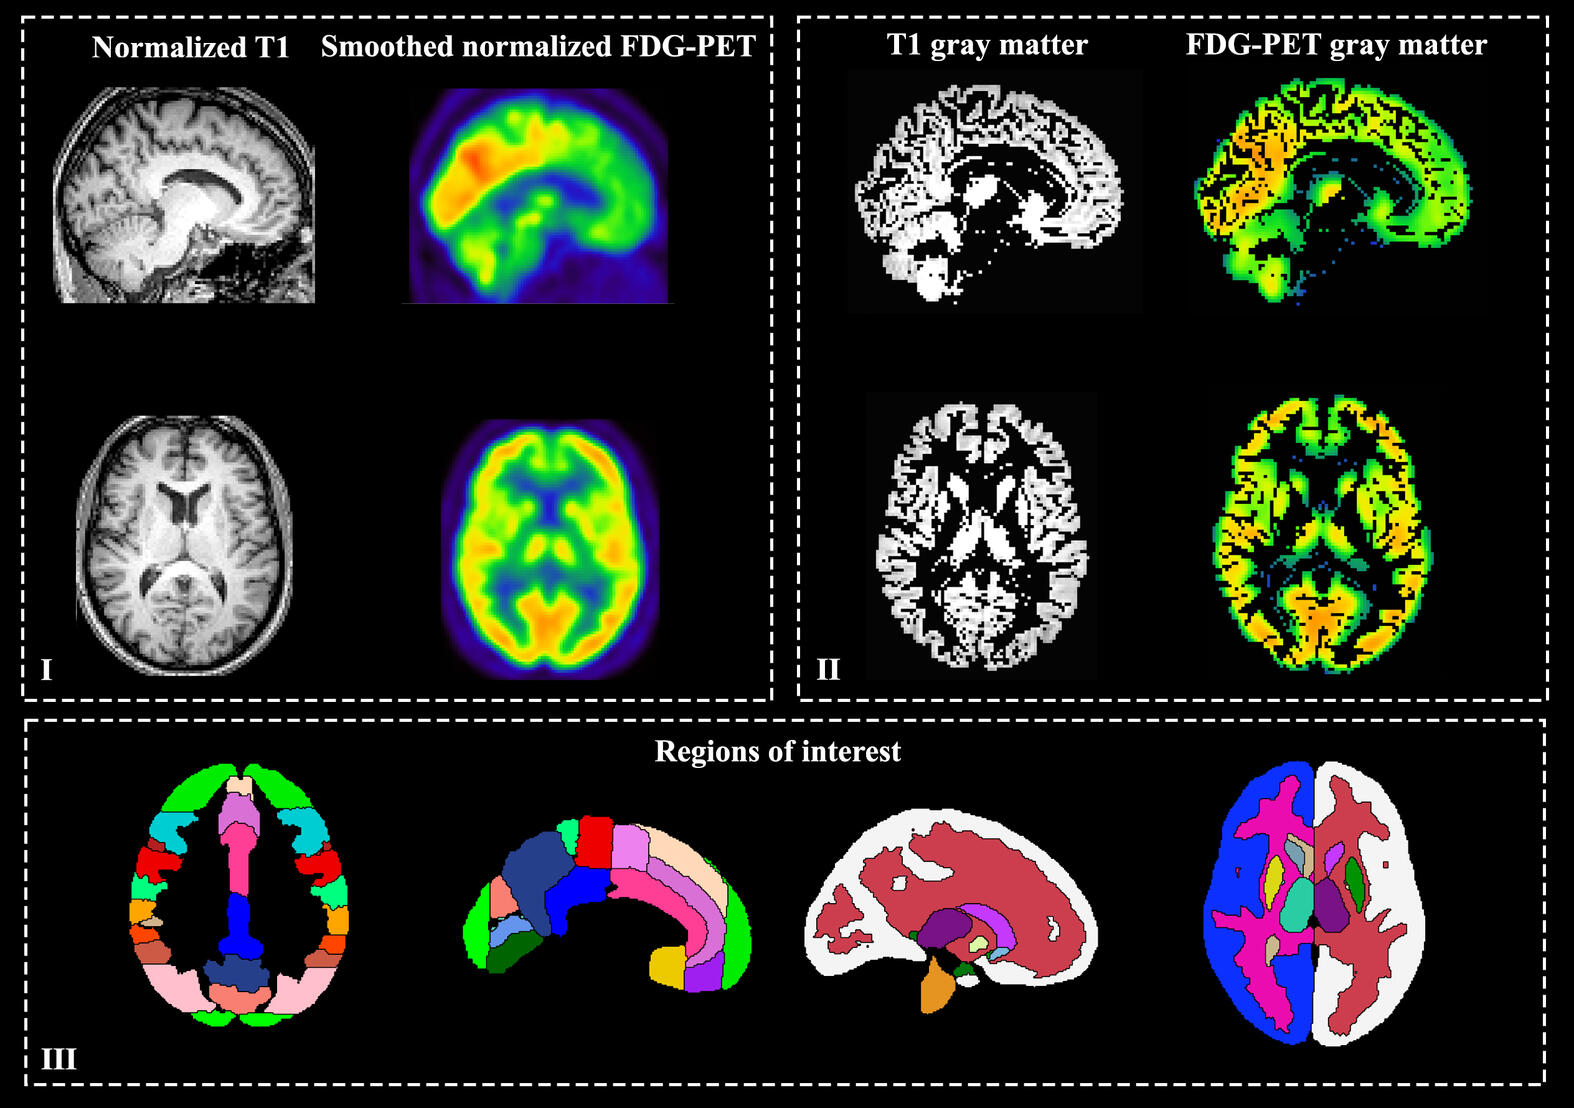

Processing of PET and MRI images such as co-registration, normalization to the standard space, tissue segmentation, and ROI definition.

Brain Extraction(skull removal)Co-registrationof PET images to T1-weighted MRI spaceSegmentationinto gray matter (GM), white matter (WM), and cerebrospinal fluid (CSF)Normalizationto a standard template space for group-level analysisRegion of Interest (ROI) Segmentationtailored to your study design